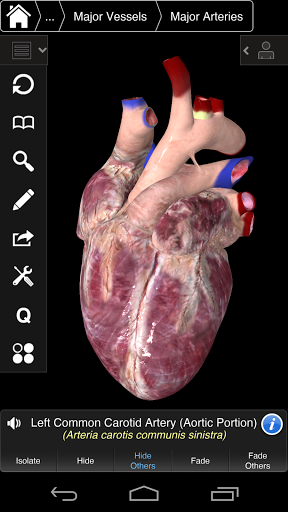

⁃ comprend également le cerveau et le cœur

---- Mode de sélection multiple - Masquer / Fondu / Isoler des structures individuelles ou multiples

---- Corriger la prononciation audio pour chaque structure

---- Nomenclature latine pour chaque structure anatomique